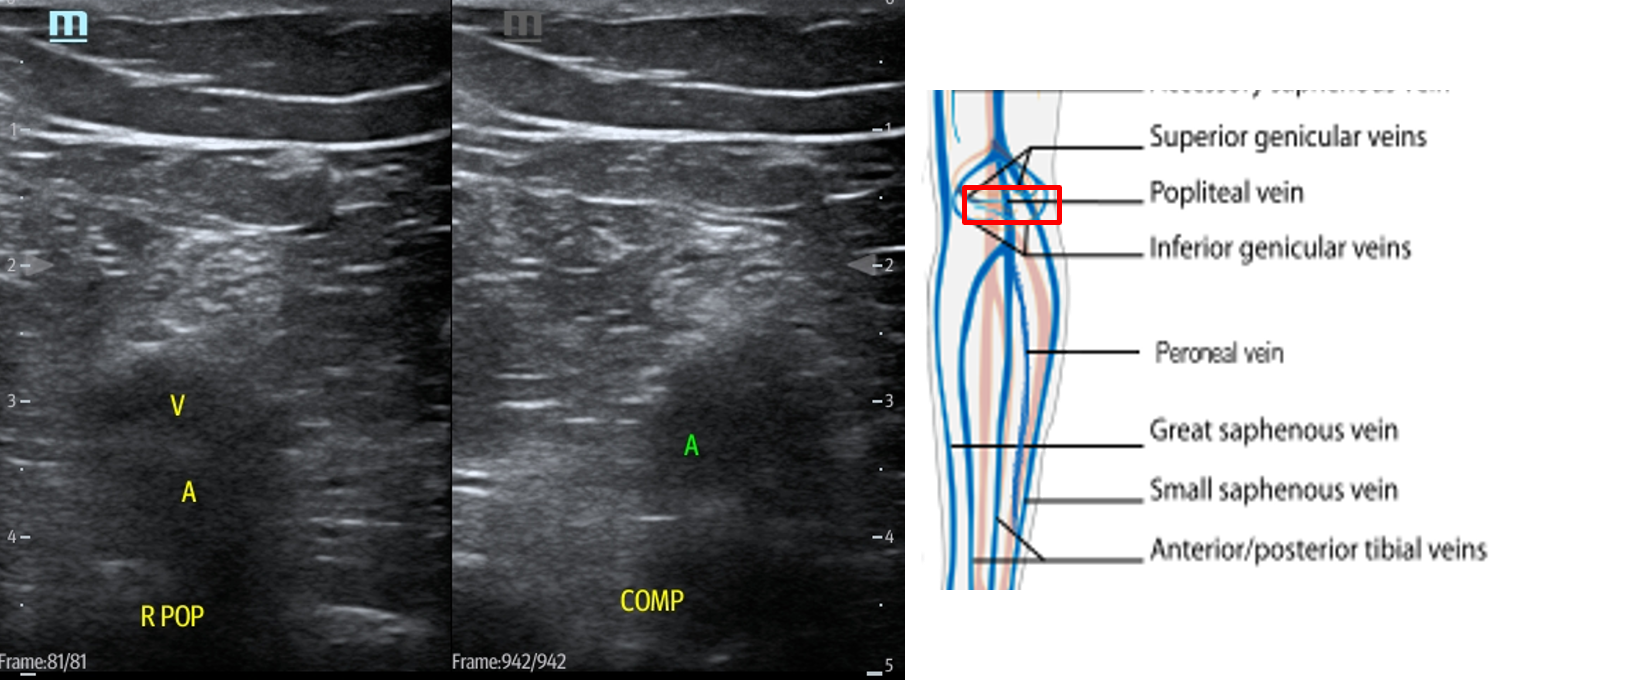

dvt ultrasound vein artery lower large study start vascular probe

vein dvt popliteal thrombosis artery compression